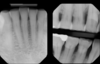

Useful imaging technique for detecting location of supernumary teeth in the mandible

Occlusal

Radiographic examination technique that is useful to determine the location of supernumary teeth location in the maxilla

SLOB rule